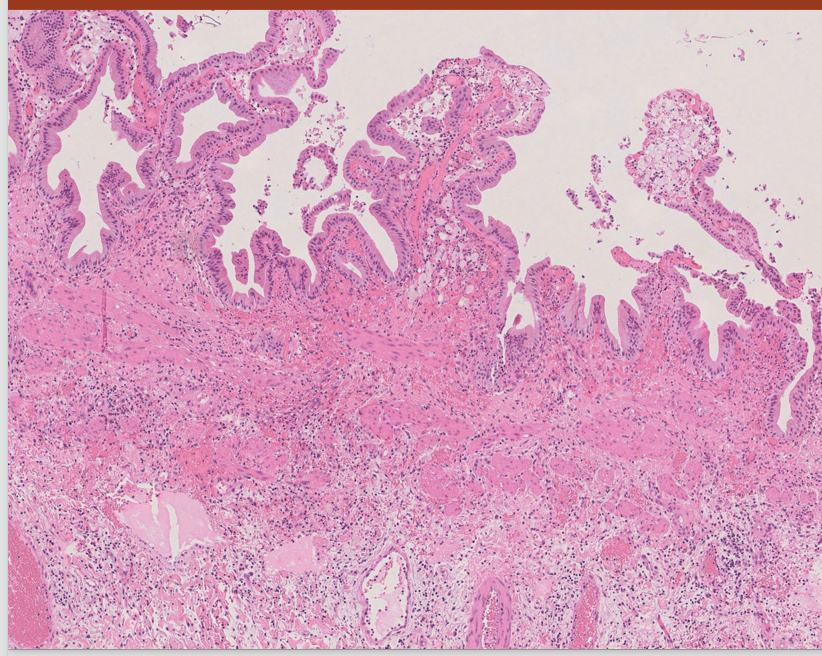

What is this?

Chronic calculus cholecystitis =Chronic cholecystitis is swelling and irritation of the gallbladder that continues over time.